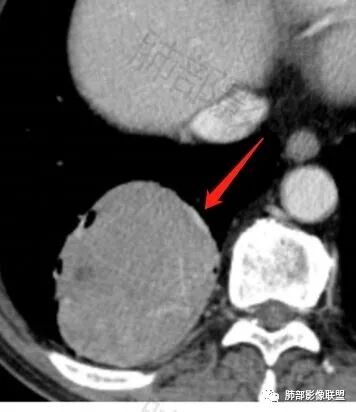

这条血管哪里来的?需要交代一下

这些是什么呢?

含气组织

受压推移

常规肿瘤如果背侧胸膜来源,肿瘤与胸膜之间不应该夹杂含气支气管,会推移

但是肺内可以将支气管外推,夹在胸膜之间

与膈面胸膜类似推断

支持肺内

但是这条血管需要交代一下:

如果这是同一根肺动脉,支持PSP

因为肺门区来源肺动脉